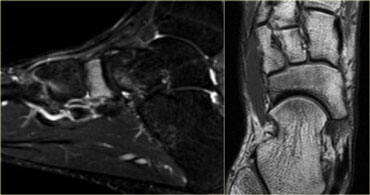

Grade 3 stress fracture of the tarsal navicular bone. Grade 3 stress fracture of the tarsal navicular bone.

Tarsal bones

The navicular bone is the most common site for stress fractures of the tarsus.

On the left a 16-year old male athlete with a high weekly mileage.

He complained of a recent onset of midfoot pain during training, lasting for several hours afterwards.

There is high signal intensity in the navicular bone on the sagittal STIR-image.

On the axial T1WI there is low signal intensity, but no definite fracture line.

Stress fracture of sesamoid of great toe: sagittal STIR and axial CT. Stress fracture of sesamoid of great toe: sagittal STIR and axial CT.

Sesamoid bones

Sesamoid bones are uncommon sites for stress fractures.

On the left a 14-year old male soccer player with persistent plantar forefoot pain.

Stress fracture of the medial sesamoid of the great toe is indicated by a high signal intensity on an MR sagittal STIR-sequence at presentation.

A CT performed at presentation shows sclerosis of the medial sesamoid and confirms the diagnosis of stress fracture.